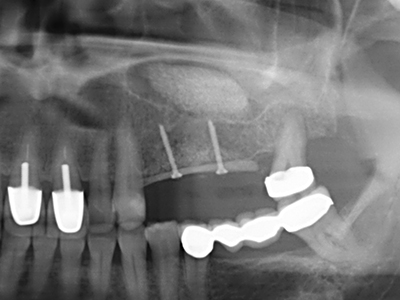

Indication: Sinus lift

Preparation of the lateral window during an external sinus floor elevation is challenging, particularly for implantologists with little surgical experience. Removal of the bone cover of the sinus without injuring the underlying Schneiderian membrane is only part of the operation – after establishing an adequate access, the membranous lining of the sinus must be carefully mobilized to make space for the augmentation materials or the implants. Piezo surgery is useful for this indication in two ways: diamond-coated instruments can be used for selective bone ablation and the underlying mucous membrane remains intact when the procedure is done carefully. The ultrasonic frequencies also enable detachment of the mucous membrane without complications – the frequencies are transmitted into the space between the mucous membrane and sinus floor by special blunt attachments (Cassetta, Ricci et al. 2012, Pereira, Gealh et al. 2014) (Rickert, Vissink et al. 2013). As a result, it is not surprising that current reviews of external sinus floor elevation positively evaluate the use of piezoelectric devices as well as the use of roughened implant surfaces and bone replacement materials (Wallace, Tarnow et al. 2012).

When surgical procedures are performed on bone in the immediate vicinity of sensitive structures such as blood vessels or nerves, rotary instruments pose a significant risk of iatrogenic injury. Piezoelectric devices can be helpful for preparation of bone covers and removal of hard tissue close to nerves, particularly for exposure of nerves after iatrogenic injury but also during nerve lateralization for resective and reconstructive procedures or implant placement (Fig. 17-20). Light contact between the piezotip and the nerve does not generally result in damage but proceeding incautiously with saw-like motions or attachments where a residual bone substrate remains may cause temporary or even permanent nerve damage. However, the risk of damage is considered to be substantially lower than when using saws or milling instruments (Pereira, Gealh et al. 2014).

As shown in the past, basically any bone surgery procedure represents a possible indication for piezo surgery. Thus preparation of the mobile segment in distraction osteogenesis (Fig. 23-25) and sandwich osteotomy uses special attachments without endangering the blood supply to the crestal section, which is essential for the success of both techniques (Gonzalez-Garcia, Diniz-Freitas et al. 2008).

There are additional applications in sinus surgery. Pathologies and foreign bodies can be removed from the sinus after concentric preparation of a generally trapezoid bone cover in the facial sinus wall. The bone cover is repositioned on conclusion of the intra-antral operation component and secured by wedging or adaptive sutures to prevent dislocation.

Purely orthodontic indications include orthognathic surgery, genioplasty (Fig. 27-30) and orbital decompression in patients with advanced endocrine orbitopathy as a result of Basedow’s disease (Ponto, Zwiener et al. 2014). Piezo devices are also used in maxillofacial surgery and to remove tumours at the base of the skull in various hospitals.